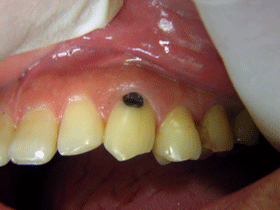

当院では取り残ししない様、肉眼的・触知的確認だけでなく虫歯検知液を使ってチェックします

またできる限り虫歯の状態も口腔内カメラで撮影した画像をお見せして治療します

う蝕検知液 光学式う蝕検出器